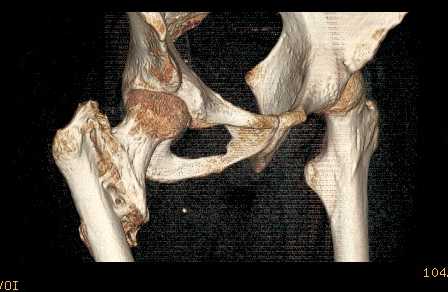

Доброго времени суток, уважаемые коллеги! Больному 45 лет. Лечили в сельской больнице на скелетном вытяжении 6 нед. по поводу межвертельного перелома бедренной кости с последующим наложением кокситной повязки еще на 2 мес.

С момента травмы прошло 5 месяцев, ходит с костылями без нагрузки, контрактуры в коленном и в тазобедренном суставах. Снимки во вложении. У нас мнения разделились. Показанием для открытого остеосинтеза мы считаем неустраненное ротационное смешение дистального фрагмента, которое может привести к нарушению биомеханики в тазобедренном суставе с последющими вытекающими последствиями.

ЭОП на сегодняшний день недоступен нам, а остеосинтез угловыми пластинами, что можно попытаться, имеет определенный риск. Как быть? Начать разработку в суставах и активизировать больного, что не было сделано до этого, или всё-таки оперировать? Будем рады Вашим советам.